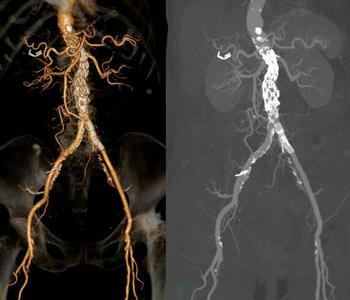

术后复查CTA提示支架形态良好,夹层封堵满意,管腔通畅。